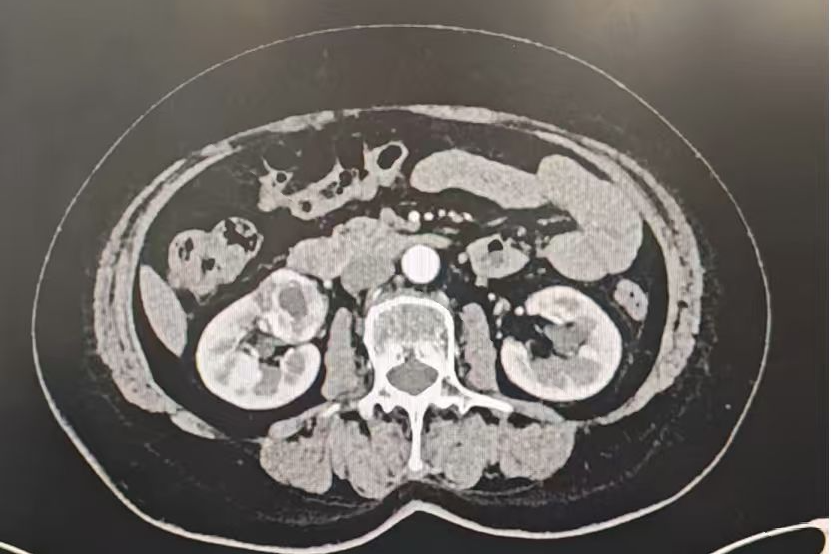

患者崔女士,62岁,因查出右肾3.9cm肿瘤入院,合并高血压、糖尿病肾病并肾功能轻度不全,影像学检查显示肾肿瘤紧贴肾门大血管及输尿管,按传统的手术方法,需根治性肾切除,但术后存在着较高的肾功能损伤风险。泌尿外科史建华主任团队创新应用第四代达芬奇Xi手术机器人系统,借助其10倍超清3D视野精准辨识肿瘤与血管及输尿管边界,凭借7个自由度仿生机械臂实现毫米级精细剥离,历时25分钟完整剜除肿瘤,创面精准缝合,术中出血极少,患者术后肾功能指标完全正常。